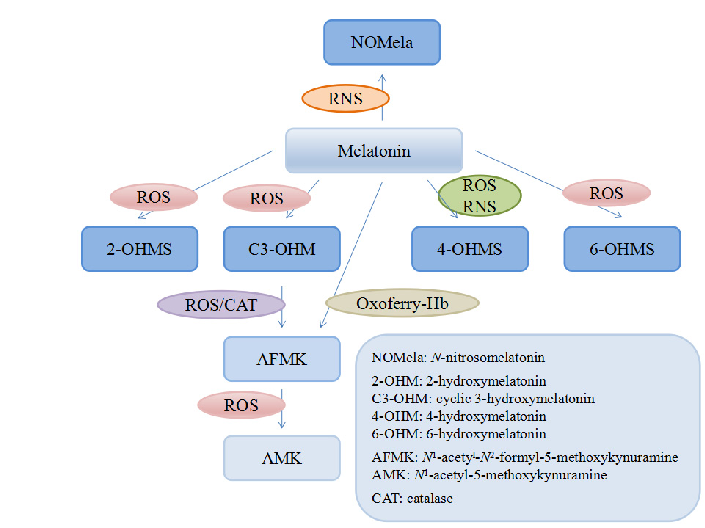

Melatonin and its metabolites including 6-hydroxymelatonin, AFMK, and AMK are structurally depicted, illustrating the biotransformation cascade.

Dietary Sources and Bioactivities of Melatonin.